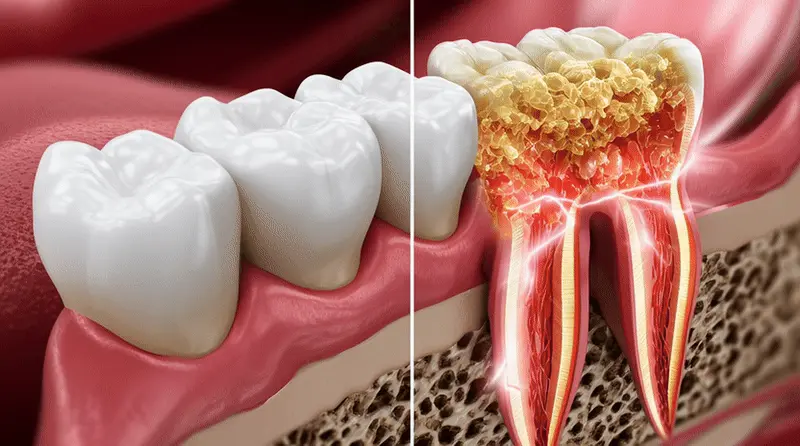

The Foundation of Your Smile: Understanding Tooth Support

Your teeth aren’t just sitting in your gums like fence posts in soft soil. They’re anchored by a complex support system that includes the periodontal ligament, cementum, and most importantly, the alveolar bone.

This bone literally holds your teeth in place, providing the solid foundation necessary for normal chewing, speaking, and smiling functions.

When this support system becomes compromised—whether through periodontal disease, trauma, or other factors—teeth begin to lose their stability. What starts as barely perceptible movement can quickly progress to noticeable looseness, and eventually, tooth loss becomes inevitable.

Bone Loss Accelerates: When a tooth is loose, it’s no longer providing the normal stimulation that keeps the surrounding bone healthy and dense. This lack of stimulation causes the bone to begin resorbing (dissolving away), creating even less support for the tooth. It’s a vicious cycle that rarely reverses on its own.